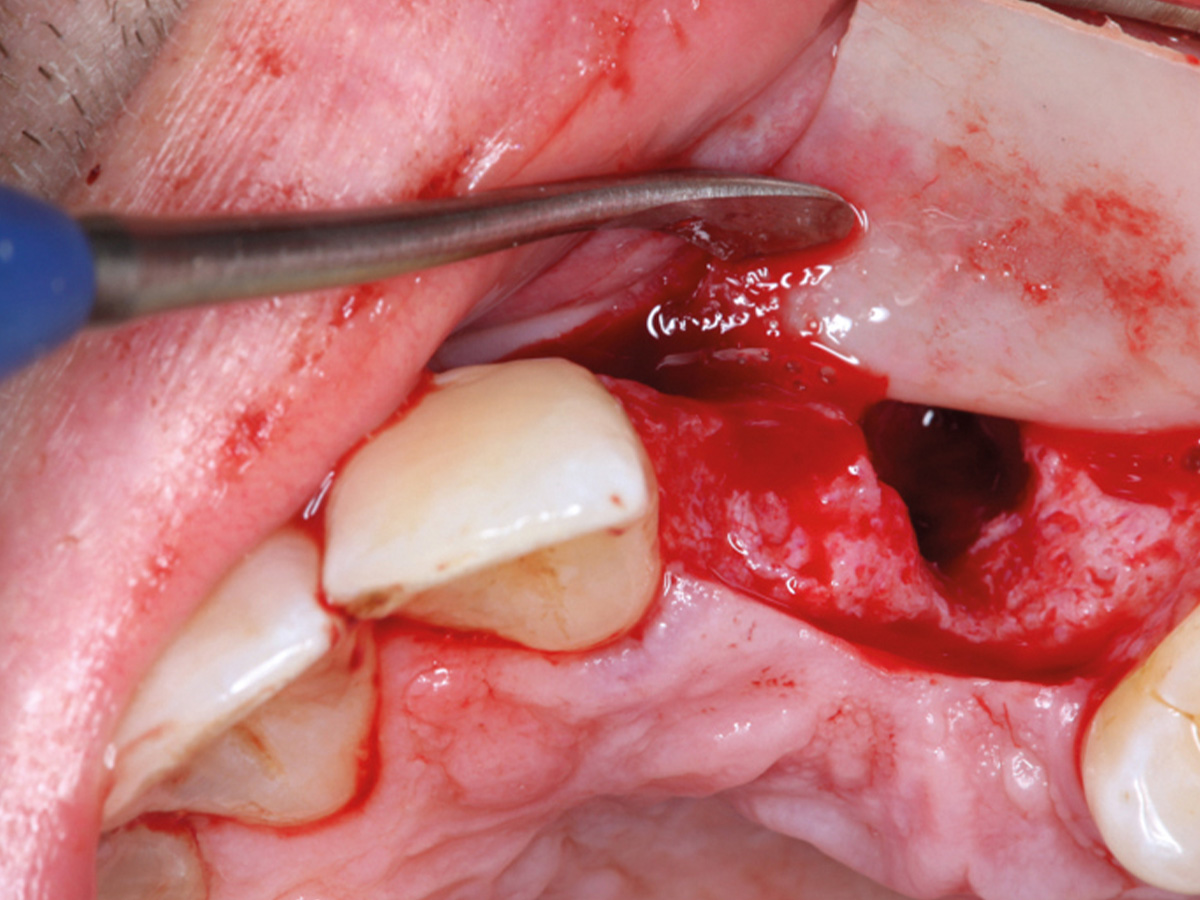

Abbildung 10

Eigenknochen mit OsteoBiol Apatos Mix.

Abbildung 11

Auffüllen des Defekts mit einem Gemisch aus Eigenknochen und OsteoBiol apatos Mix.